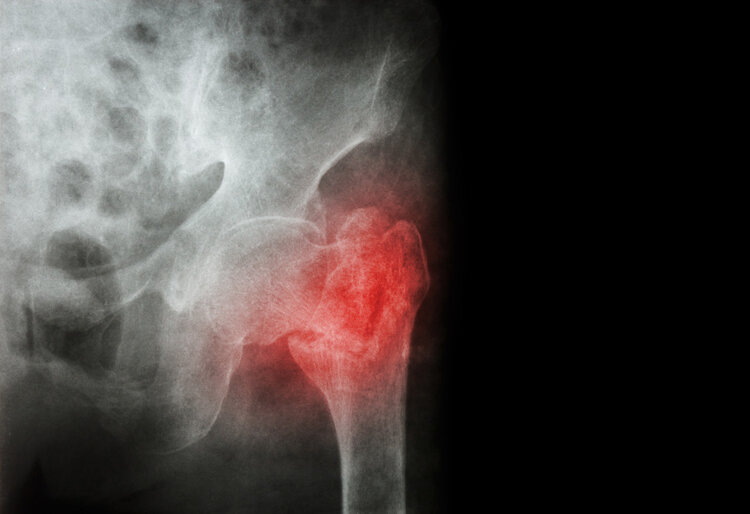

接着李大爷就被家人送到医院检查 , 诊断是左股骨颈骨折 , 然后进行住院治疗 , 在医生的建议指导下 , 家属同意李大爷接受人工全髋关节置换手术 。

在我国 , 65岁以上的老年人伤害死亡的首要原因是跌倒 。 因为跌倒很容易引发骨折 , 主要骨折部位是脊椎骨、髋关节以及手腕等 , 最严重的是髋关节骨折 , 通常发生髋关节骨折的老年人 , 在一年内的死亡率超过了20% , 甚至能达到50% 。 也被成为人生的最后一摔 。

随着年龄的增长 , 老年人的骨骼脆性增加、韧性差 , 而且容易有骨质疏松的情况 , 所以受到轻微的外伤就可能会导致骨折 。 老年人骨折通常容易发生在腕部、脊椎和髋部 , 而引起骨折的根本原因就是骨质疏松 。

骨质疏松症是因为骨组织微结构损坏、骨量减少而导致增加了骨脆性 , 所以非常容易发生骨折 。 骨质疏松性骨折通常也称为脆性骨折 , 是指在日常活动或受到轻微外伤时就发生骨折 , 在多种骨质疏松骨折中 , 脊椎椎体骨折最为常见 , 最严重的是髋部骨折 。